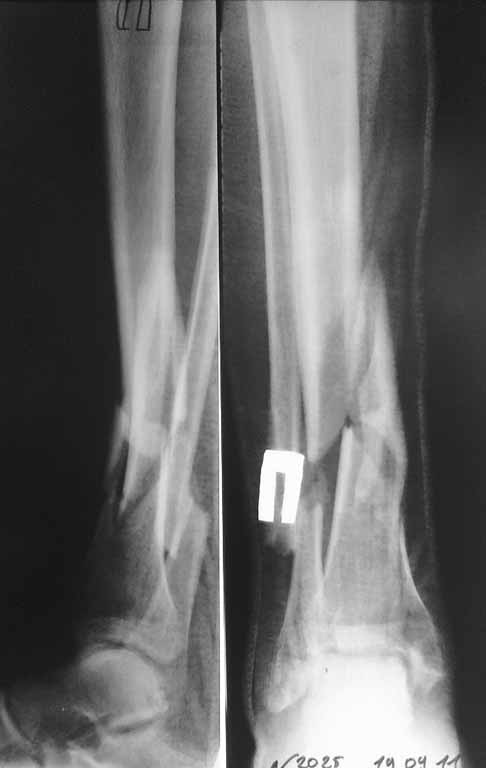

спасибо за участие. Перелом голени выложил сегодня из-за проблем с интернетом. На этой неделе запланирована попытка синтеза бедра, длинный PFN ChM, на ортопедическом столе, все-таки планирую открывать зону перелома сразу. Голень на следующей неделе.

Я бы порекомендовал, если кожные покровы голени позволяют- произвести остеосинтез пластинами через общий передне-наружный доступ. И в первую очередь зафиксировать полутрубчатой 4,5мм или компрессионной 3,5мм пластиной АО перелом н/3 малоберцовой кости, чтобы стабилизировать отломки б/берцовой по длине.

Если с кожей не то- попытаться получить репозицию под ЭОП-ом и наложить аппарат АО до голеностопного сустава (собирать Илизаров - долго, нудно, да и, наверное нет необходимости...)

Уважаемый Сергей! Следует уточнить(для уважаемого сообщества) , что переломы находятся на разных конечностях, поэтому восстановление длины бедра потребует равнозначной коррекции длины голени. Либо, как предлагает профессор Djoldas Kuldjanov, не добиваться полной репозиции и пожертвовать частью дистального отломка, сохранив ось и ротацию. Корригировать длину голени проще ввиду меньших усилий по преодолению ретракции мягких тканей. Хотя пациент молодой и желательно наиболее полно восстановить конечности. Несомненно,аппарат Илизарова собирать долго и нудно и неохота, но возможность управляемой фиксации при минимальных экономических затратах перевешивает данные "недостатки". Да и не располагаем АО фиксаторами, гексаподами. Следует учесть и то , что при одномоментной коррекции длины голени (3,5 - 4 см) могут возникнуть трудности с зашиванием и заживлением операционных доступов. Еще позволю уточнить, что клинических признаков консолидации на голени нет - подвижность полная, что не потребует остеотомии малоберцовой кости. Поэтому желаю Вам, Сергей, удачи в одномоментной коррекции деформации бедра и остеосинтезе, но нужно быть готовым к варианту Александра Николаевича - дистрактор, дозированная коррекция смещения по длине, остеосинтез.

5.10.2011 синтез правой голени стержнем Деост, в закрытую с применением дистрактора и остеотомией малоберцовой кости. Снимки в приложении. Пациент активизирован, начал передвигаться на коляске, сегодня встал с костылями.